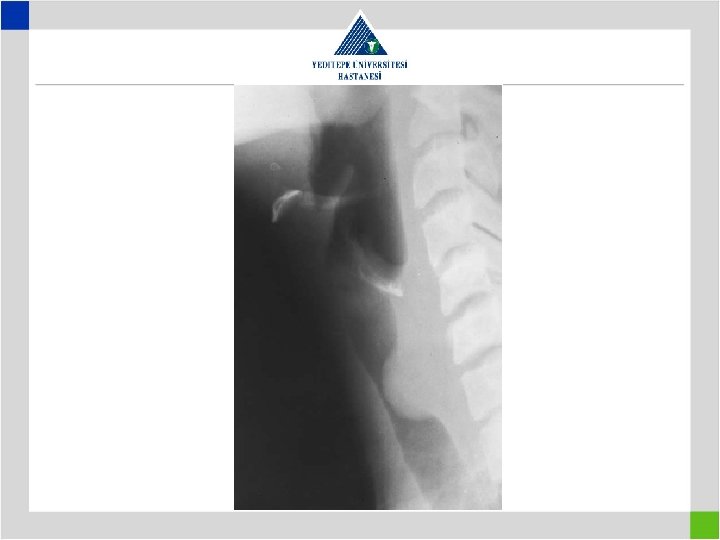

Diagnosis • Preop glottic insufficiency to be searched – Preop awake laryngoscopy – Preop work-up for presence of aspiration – Tracheostomy means previous intubation – look for a distal second lesion – Vocal cords do not move both in paralysis and cricoarythenoid arthritis or traumatic ankylosis

Diagnosis • Stenotic segment calculation to be correct • CT image in supine position may falsly indicate a preglottic stenosis – Overresection – increased anastomotic tension – restenosis • Pediatric trachea tolerates the tension poorly in comparison with adults – Insufficient resection – remaining fibrosis – restenosis